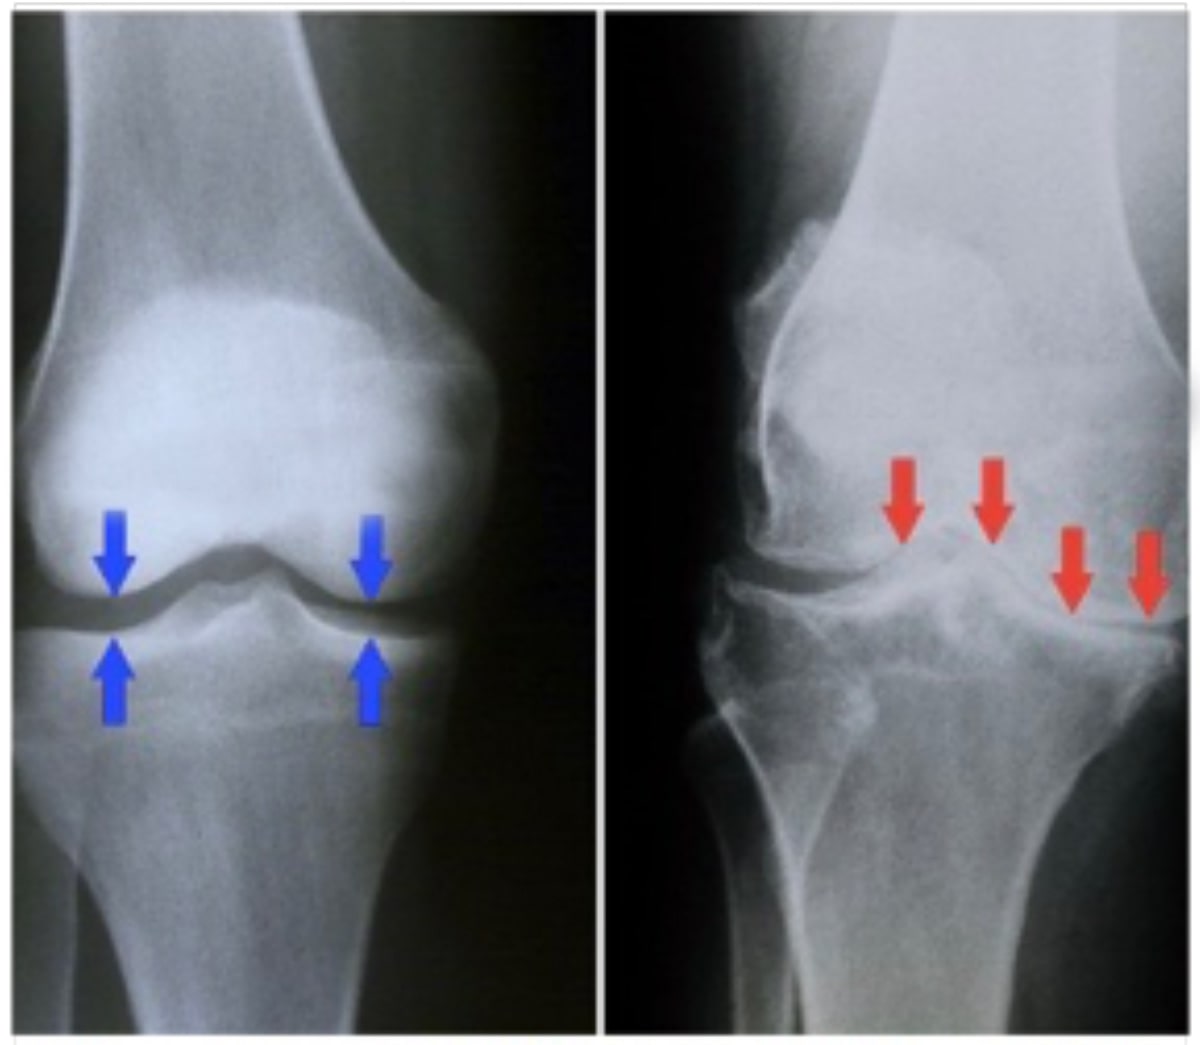

- Røntgenstråler. Disse avbildningstestene gir detaljerte bilder av tette strukturer, som bein. De kan bidra til å skille mellom ulike former for leddgikt. Røntgenbilder av et leddgikt kan vise en innsnevring av fellesrommet, endringer i beinet og dannelsen av bensporer (osteofytter).